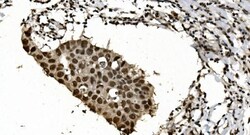

Adding 0.2 mL of distilled water will yield a concentration of 500 μg/mL. Positive Control - WB: human Jurkat whole cell, human PC-3 whole cell, human Raji whole cell, human K562 whole cell, human Caco-2 whole cell, human MCF-7 whole cell, human HL-60 whole cell, human PC-3 whole cell. IHC: human breast cancer tissue, human gastric cancer lymph node tissue, human liver cancer tissue, human ovarian serous adenocarcinoma tissue, human pancreatic cancer tissue, human placenta tissue, human rectal cancer tissue. ICC/IF: MCF-7 cell. Flow: K562 cell. Store at -20°C for one year from date of receipt. After reconstitution, at 4°C for one month. It can also be aliquotted and stored frozen at -20°C for six months. Avoid repeated freeze-thaw cycles.

| Applications | ELISA, Flow Cytometry, Immunohistochemistry (Paraffin), Western Blot, Immunocytochemistry |